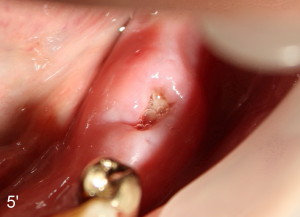

Postoperatively, there is minimal pain for Mr. Lip. The patient rinses with Chlorhexidine, although he does not take Amoxicillin. Luckily, there is no sign of infection either in #30 implant placement area (Fig.5, wound dehisces after suture removal), or in the extraction sockets (Fig.5'), one week postoperatively.